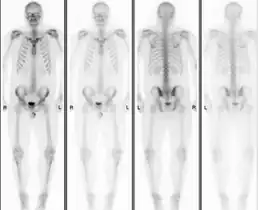

Normal bone scan in a person with osteopoikilosis

The radiographic appearance of osteopoikilosis on an X-ray is characterized by a pattern of numerous white densities of similar size spread throughout all the bones. This is a systemic condition. It must be differentiated from blastic metastasis, which can also present radiographically as white densities interspersed throughout bone. Blastic metastasis tends to present with larger and more irregular densities in less of a uniform pattern. Another differentiating factor is age, with blastic metastasis mostly affecting older people, and osteopoikilosis being found in people 20 years of age and younger.

Osteopoikilosis is a benign, autosomal dominant sclerosing dysplasia of bone characterized by the presence of numerous bone islands in the skeleton.[1]